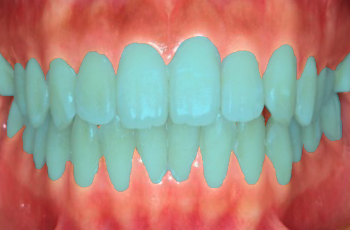

![]() |

| Upper | Front | Lower |

To enable research of computer vision methods in dentistry we have collected and annotated the TriDental dataset consisting of RGB images of oral cavities. The images were collected by medical professionals. The dataset contains images of oral cavities of 1000 individuals. Each individual’s oral cavity was photographed from three distinct views as shown in Fig. 1 resulting in 3000 RGB images.